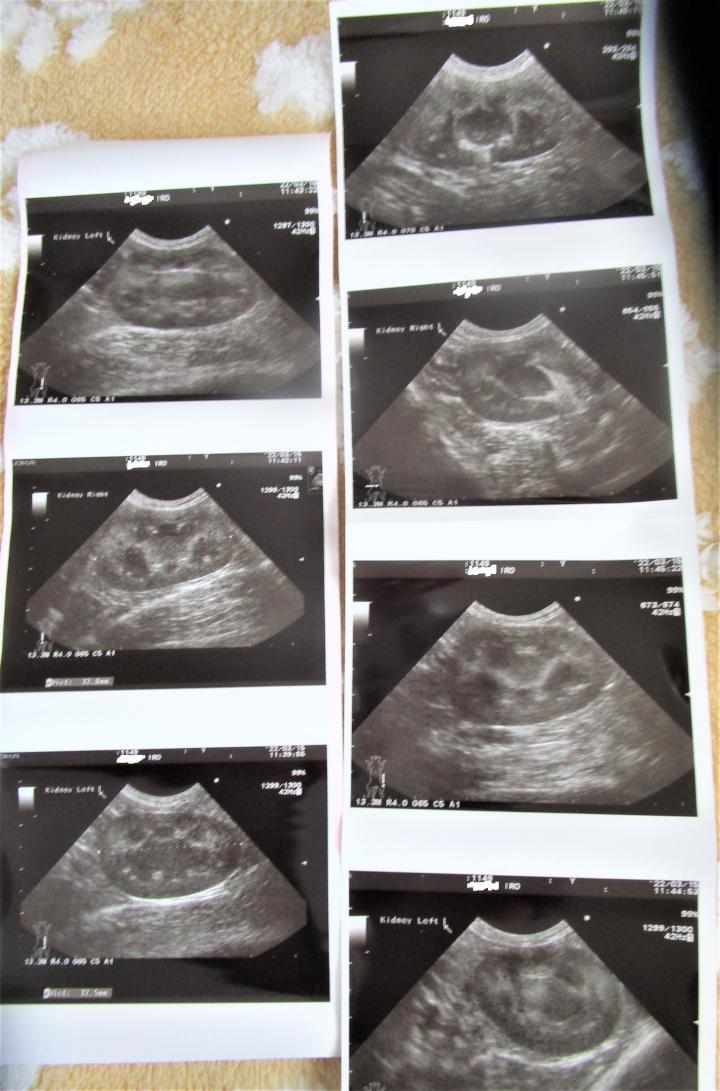

エコー結果

⇒左右ともに3.2cmレントゲンの所見と同様にこれから成長すると思われるとのコト

腎臓の自体、キレイに動いている

私が係りつけ医に見せる。と思われてかいっぱい写真をもらう。

そもそも素人が見たとて、何が何だかよくわからない。

・現時点で画像(エコー)を見る限り腎臓は正常に動いている・尿比重が低いのは、尿を濃縮できていないコト

⇒けれど、その原因はわからない